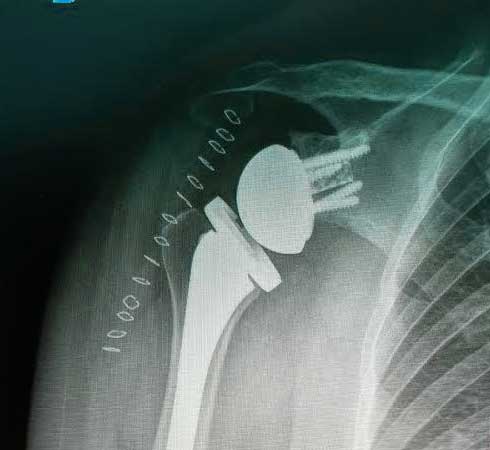

Es la sustitución artificial de la articulación por un implante de metal y polietileno indicada por artrosis, desgaste o lesión masiva del manguito rotador.

La recuperación de la cirugía reemplazo de hombro con una prótesis reversa de hombro o una prótesis anatómica de hombro va muy ligada al estado de la articulación previamente lesionada y al apego que tenga el paciente con la terapia física y así poder ofrecer una recuperación buena, muy buena o excelente.

Radiografía postquirúrgica de prótesis reversa de hombro derecho.